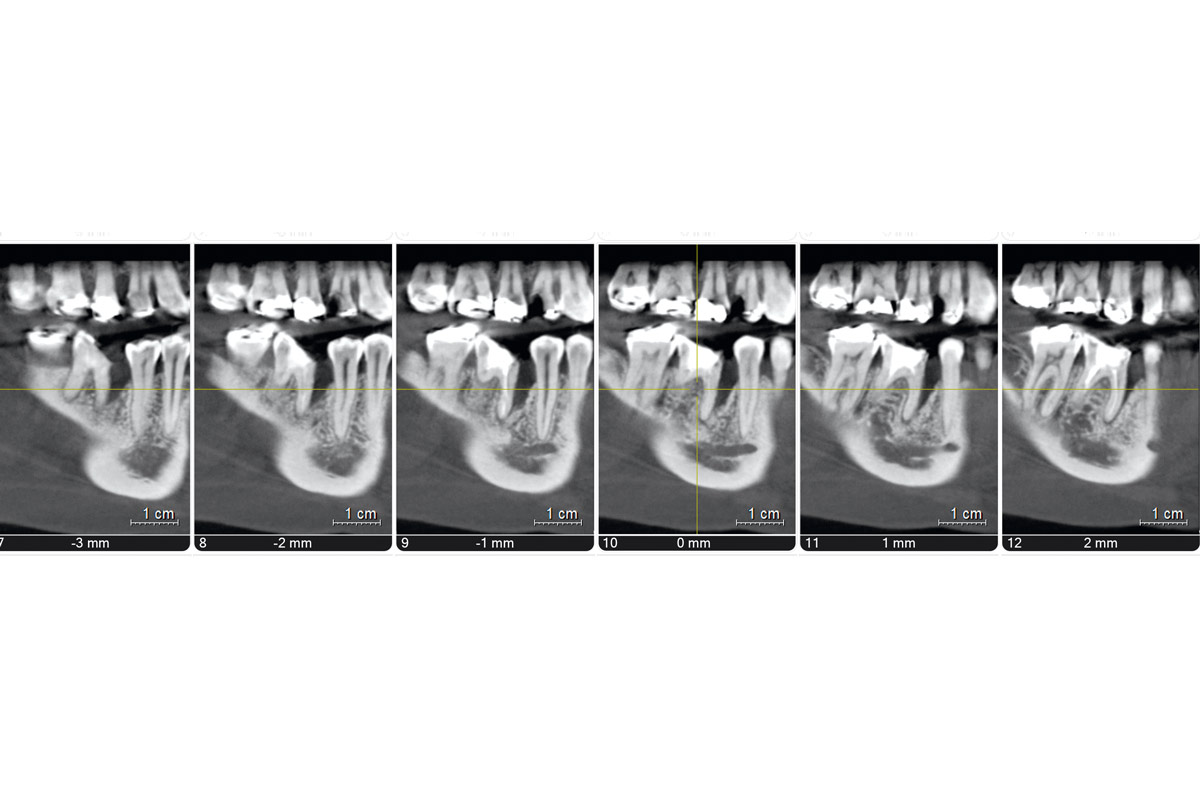

Preoperative Ortopantomogram of the teeth planned for extraction